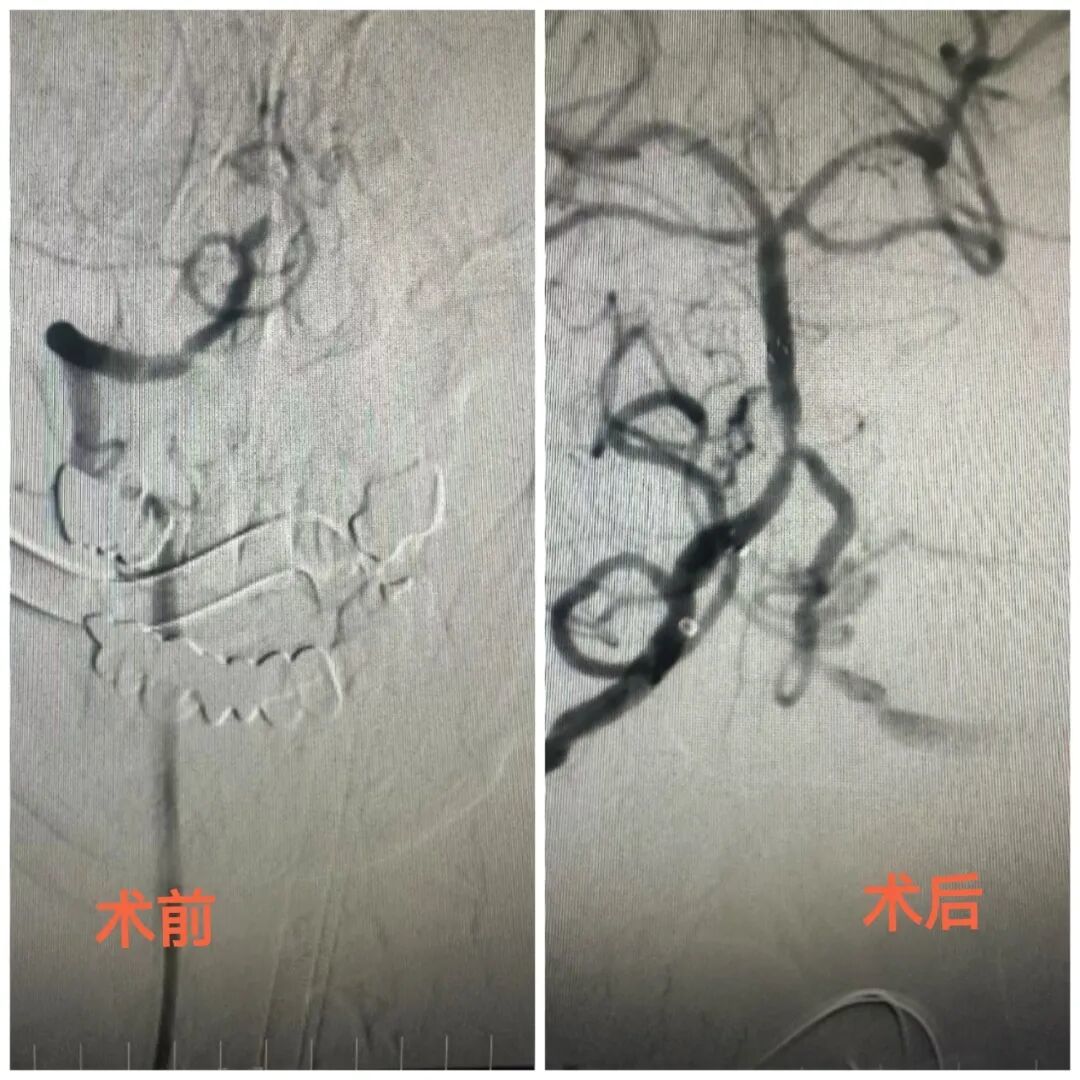

神经内科学科带头人、三病区主任贾颐教授当机立断,迅速为张先生进行了急诊血管内介入取栓手术。手术成功开通了堵塞的生命主干道,并置入支架以维持血管通畅。目前,张先生意识已逐渐恢复,正在进一步康复中。